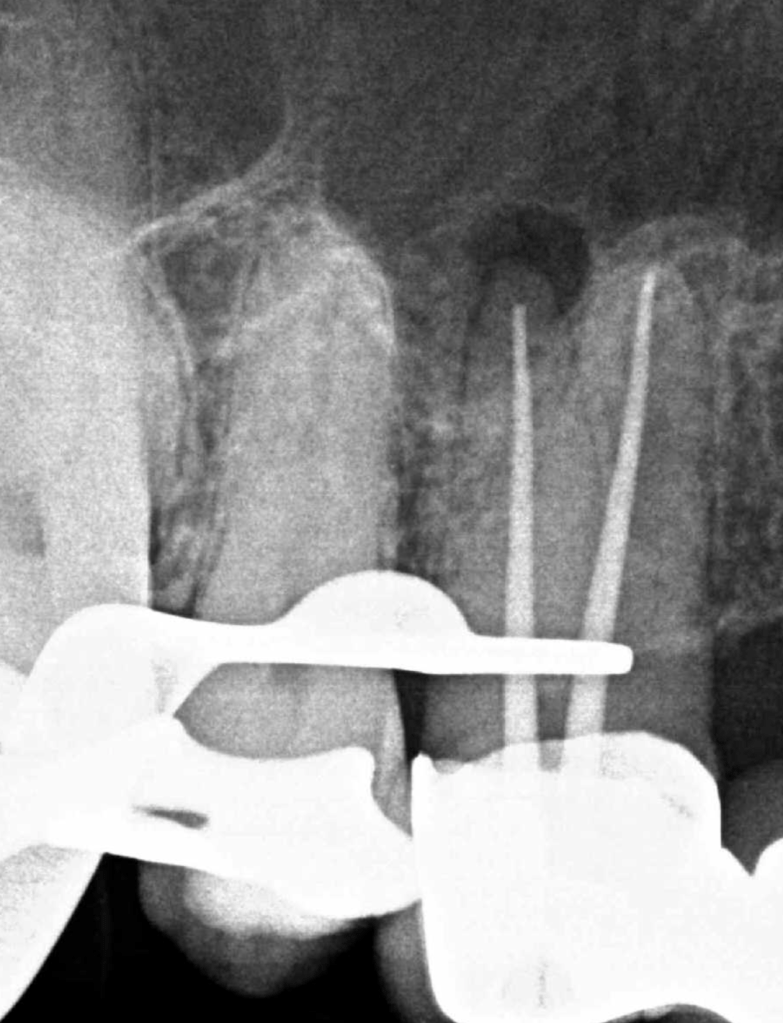

Endodoncias a traves de coronas

20 molar superior a traves de corona